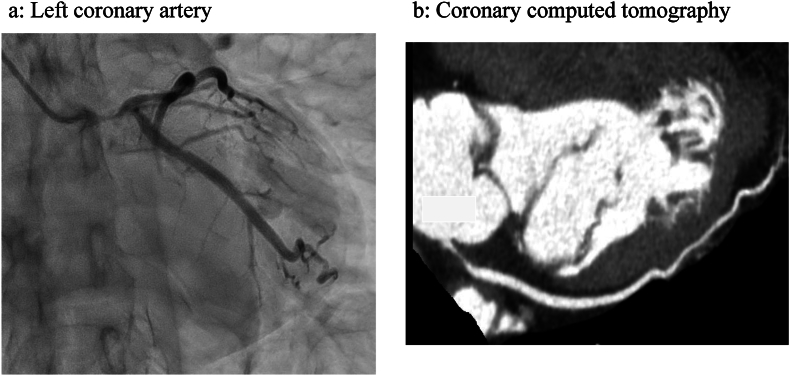

Abstract Image